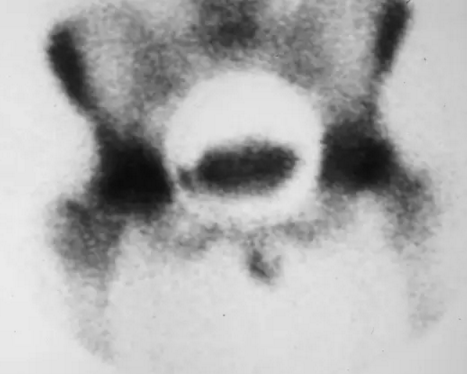

股骨头缺血坏死

骨扫描显示在右股骨头的超外侧方面的摄取增加,这表明缺血坏死,但是提供关于髋部的结构完整性的很少的信息。

骨扫描显示在两个髋部中放射性药物试剂的吸收显着增加。